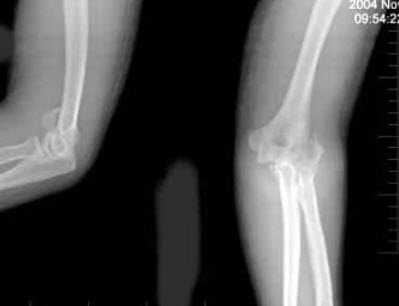

272、单项选择题

女,53岁,因摔倒时手掌着地,感右肘关节肿痛、畸形,X线摄片如图所示,正确的诊断是()

A.右肱骨外髁骨折

B.右肱骨内上髁骨折

C.右肱骨外上髁骨折

D.右肱骨小头骨骺分离

E.以上均不正确